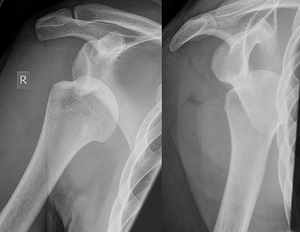

Imaging diagnosis conventionally begins with plain film radiography. Generally, AP radiographs of the shoulder with the arm in internal rotation offer the best yield while axillary views and AP radiographs with external rotation tend to obscure the defect. However, pain and tenderness in the injured joint make appropriate positioning difficult and in a recent study of plain film x-ray for Hill–Sachs lesions, the sensitivity was only about 20%. i.e. the finding was not visible on plain film x-ray about 80% of the time.[5]

By contrast, studies have shown the value of ultrasonography in diagnosing Hill–Sachs lesions. In a population with recurrent dislocation using findings at surgery as the gold standard, a sensitivity of 96% was demonstrated.[6] In a second study of patients with continuing shoulder instability after trauma, and using double contrast CT as a gold standard, a sensitivity of over 95% was demonstrated for ultrasound.[7] It should be borne in mind that in both those studies, patients were having continuing problems after initial injury, and therefore the presence of a Hill–Sachs lesion was more likely. Nevertheless, ultrasonography, which is noninvasive and free from radiation, offers important advantages.

MRI has also been shown to be highly reliable for the diagnosis of Hill-Sachs (and Bankart) lesions. One study used challenging methodology. First of all, it applied to those patients with a single, or first time, dislocation. Such lesions were likely to be smaller and therefore more difficult to detect. Second, two radiologists, who were blinded to the surgical outcome, reviewed the MRI findings, while two orthopedic surgeons, who were blinded to the MRI findings, reviewed videotapes of the arthroscopic procedures. Coefficiency of agreement was then calculated for the MRI and arthroscopic findings and there was total agreement ( kappa = 1.0) for Hill-Sachs and Bankart lesions.[8]